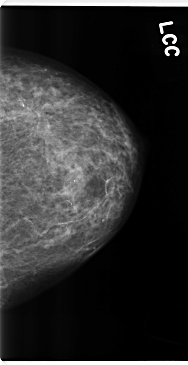

C_0184_1.LEFT_MLO

C_0184_1.LEFT_CC

LEFT_MLO LINES 4720 PIXELS_PER_LINE 2424 BITS_PER_PIXEL 12 RESOLUTION 50 NON_OVERLAY